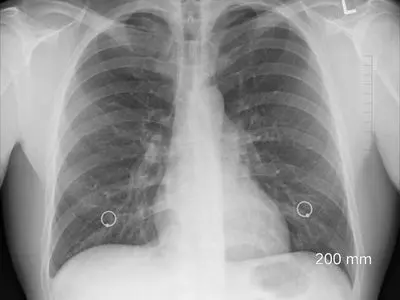

رییس انجمن علمی متخصصان ریه ایران درباره بار بیماریهای آسم و مزمن ریوی و تاثیر آلودگی هوا و دخانیات بر بروز این بیماریها توضیح داد.

رییس بخش آنکولوژی بیمارستان دکتر مسیح دانشوری، سرطان ریه را جزو شایعترین سرطانها در جهان و مصرف دخانیات را مهمترین عامل بروز آن دانست.

وزیر بهداشت گفت: بخش مهمی از اعتبارات حوزه سلامت که باید صرف بهداشت عمومی و درمان مردم شود، صرف درمان بیماری هایی که ناشی از استعمال دخانیات است، می شود.